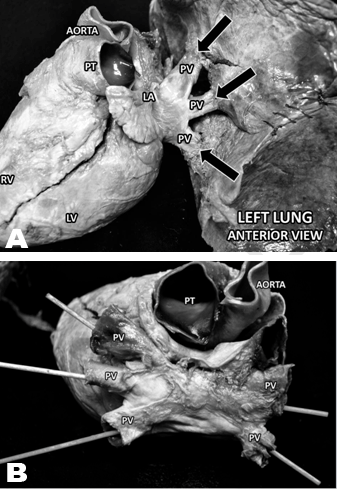

One of the principle benefits of anatomical dissection for medical students is the development of appreciation for anatomical variability and for common and unusual deviations from standard textbook depictions of anatomical structure. In the course of a single term, deviations in left pulmonary vein number were observed in 3 of 17 cadavers dissected by pre-clinical medical students at the Sanford School of Medicine. In the body of an 84-year-old female, a single dilated pulmonary vein was found connecting the left lung to the left atrium (Figure 1). Two normal pulmonary veins returned to the left atrium from the right lung. No other deviation was detected in regards to the pulmonary or cardiac anatomy. Gross anatomical dissection of an 85-year-old female revealed an identical deviation in pulmonary vein structure, with a single dilated left pulmonary vein and otherwise normal cardiovascular anatomy (Figure 2). In a third cardiovascular dissection of a 70-year-old male, three left pulmonary veins were observed (Figure 3A-B), with no additional pulmonary or cardiac abnormalities being detected. In all three instances, these abnormalities in pulmonary vein numbers appear to be congenital.

Figure 3: (A) Case 3 Anterior view of the left lung and heart of a 70-year-old male. Three abnormal pulmonary veins are observed connecting the left lung to the left atrium (black arrows). Two normal pulmonary veins connected the right lung to the left atrium (not shown). PT = pulmonary trunk, RV = right ventricle, LV = left ventricle, PV = pulmonary vein, LA = left atrium (B) Case 3 View of the heart alone of a 70-year-old male. Three pulmonary veins connecting the left lung and two pulmonary veins connecting the right lung are shown anastomosing with each other and draining into the left atrium. PV = pulmonary vein, PT = pulmonary trunk.